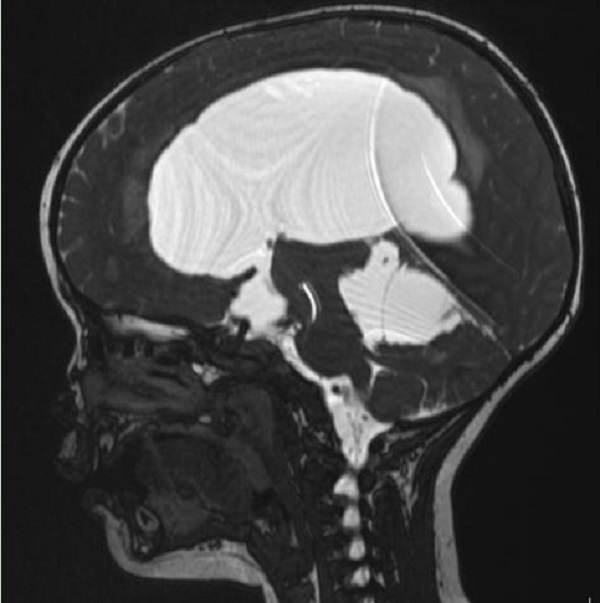

一岁多的赫赫小朋友自出生头颅就比同龄小孩大,近半月来进食后出现呕吐,伴头痛,在当地医院及省内多家医院治疗不见好转,于是来到二一五医院神经重症监护室,因患儿近半月多不能正常进食,入院时精神萎靡,头颅MRI检查提示“脑室系统扩大,双侧脑室额角周围间质水肿,左侧丘脑占位病变,鞍上池及小脑上池扩大”。

为进一步鉴别脑积水类型,行磁共振3D FIESTA序列检查可见侧脑室扩大明显,中脑导水管中段阻塞、三脑室底受压下陷,诊断梗阻性脑积水。